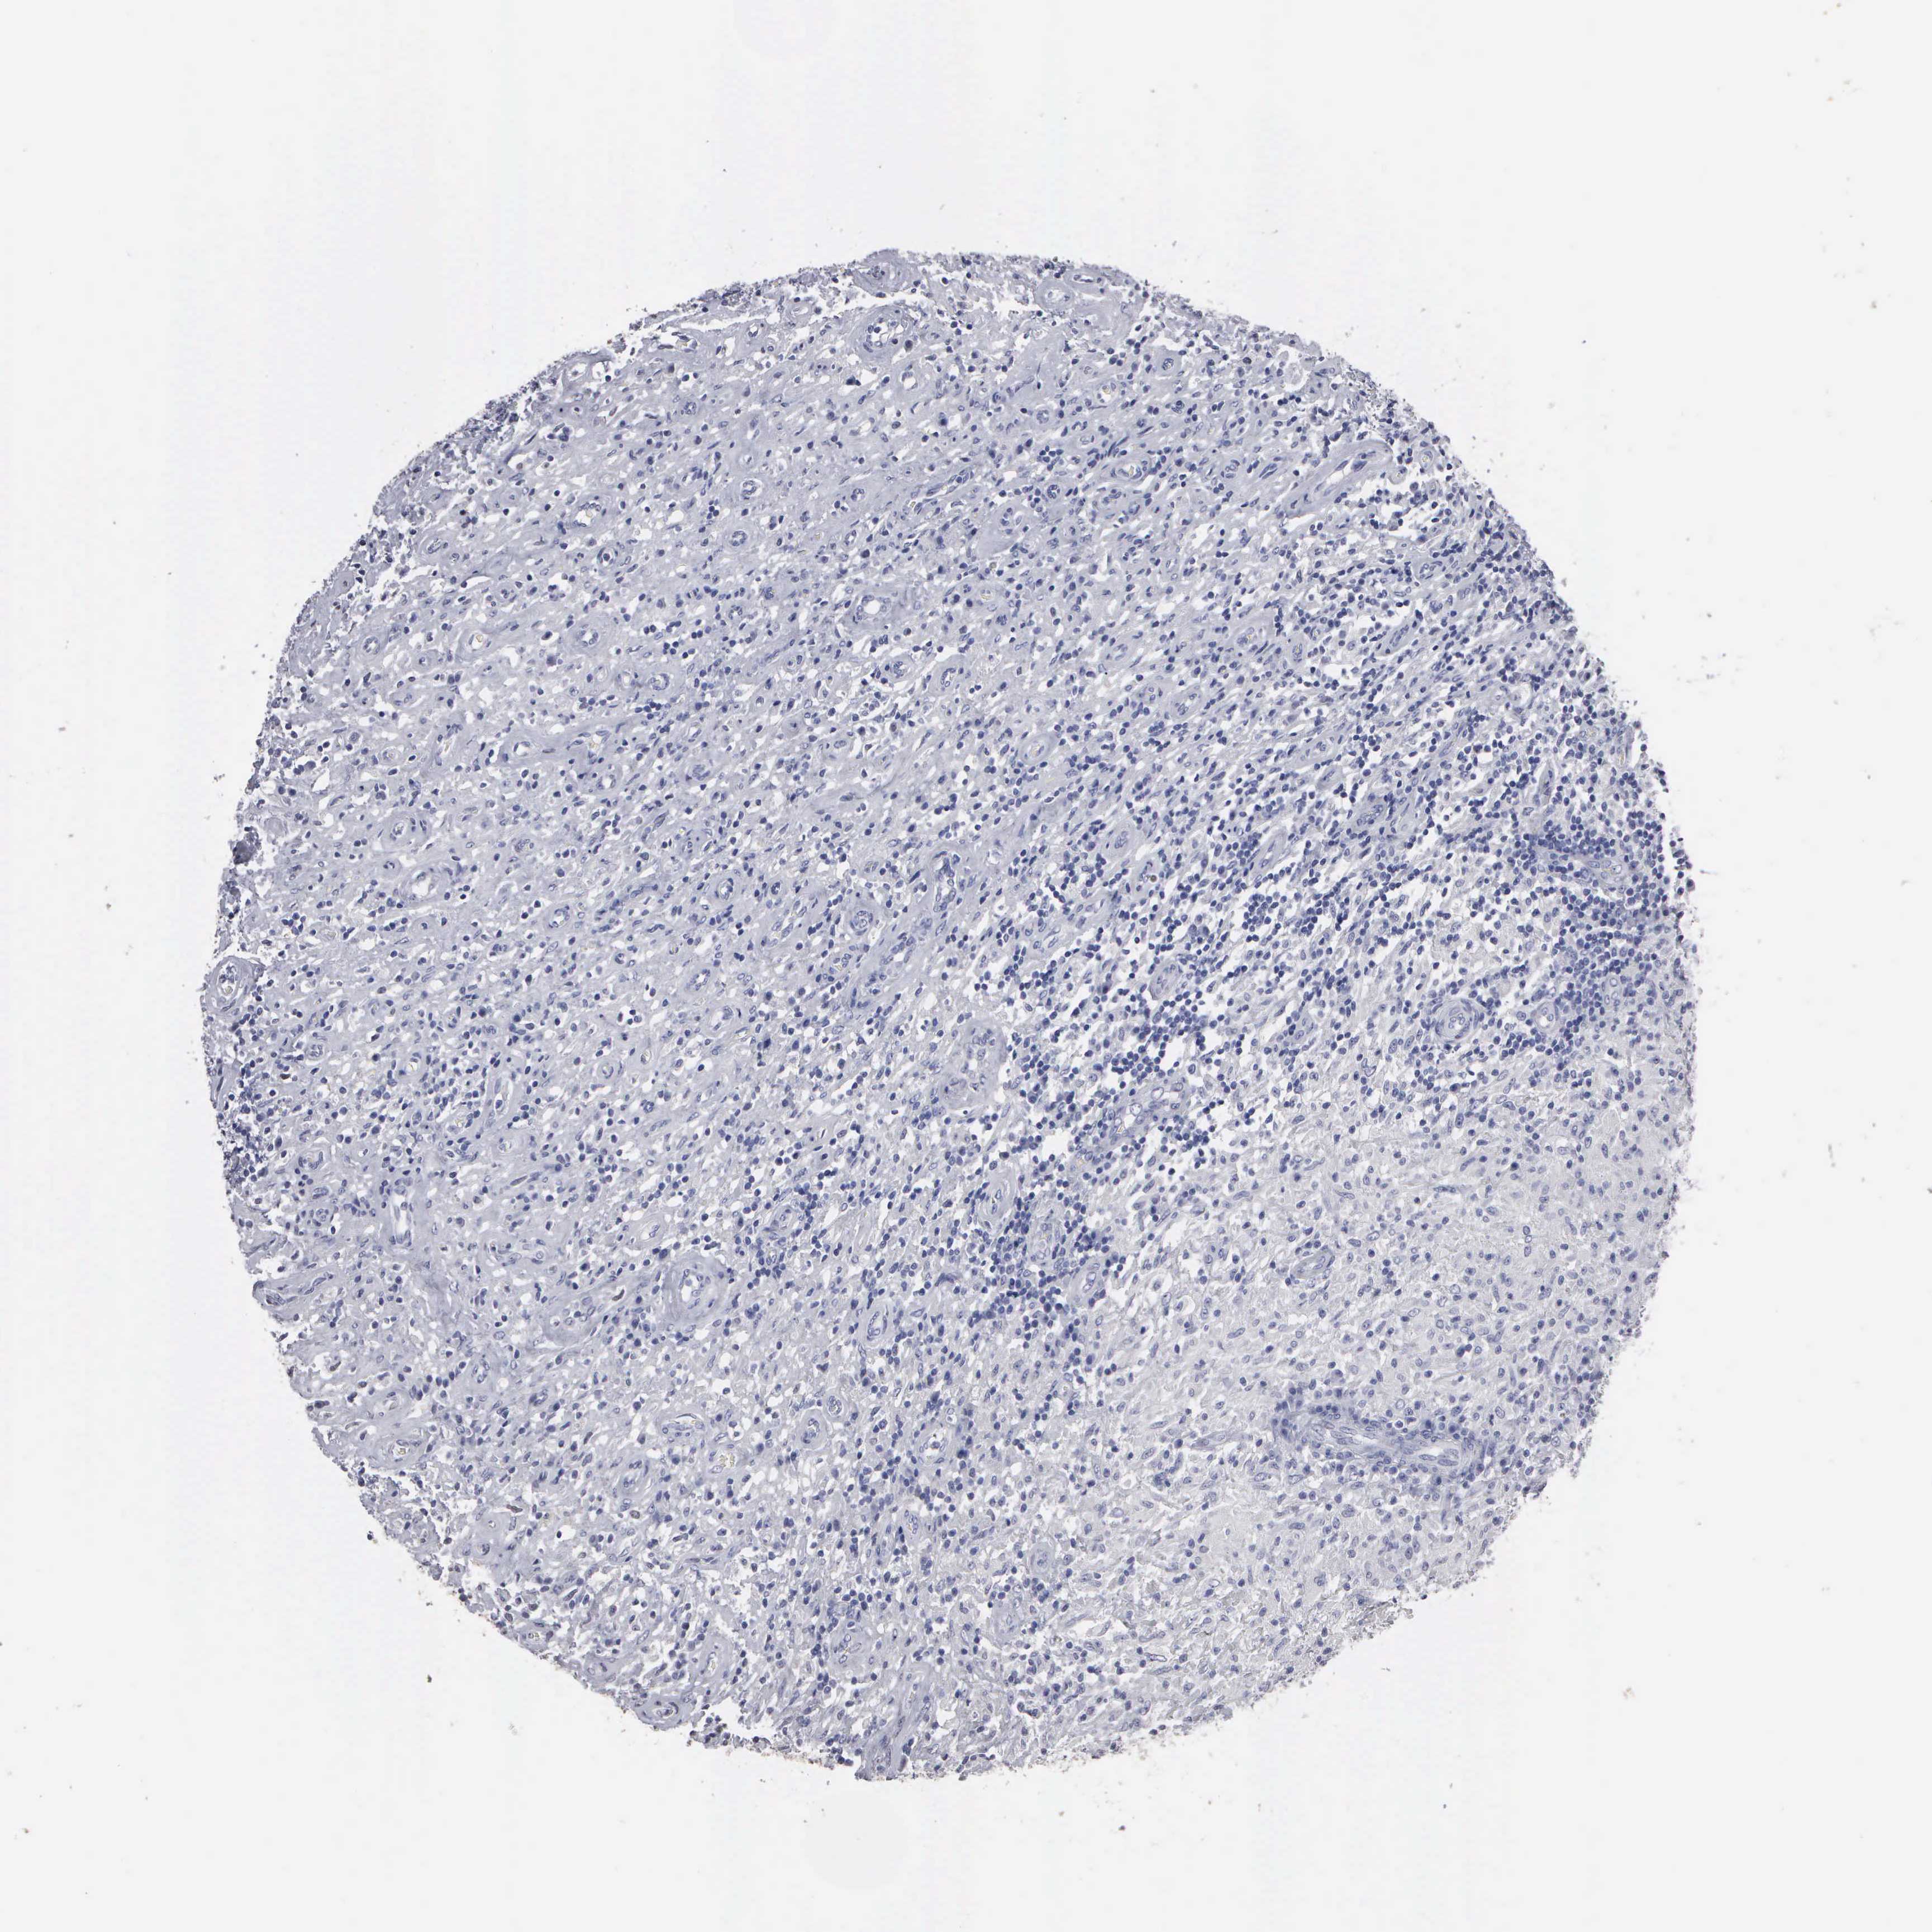

TESTIS CANCER - Protein expressioni

A mouse-over function shows sample information and annotation data. Click on an image to view it in a full screen mode. Samples can be filtered based on level of antibody staining by selecting one or several of the following categories: high, medium, low and not detected. The assay and annotation is described here.

Note that samples used for immunohistochemistry by the Human Protein Atlas do not correspond to samples in the TCGA dataset.

Antibody stainingi

Antibody staining in the annotated cell types in the current human tissue is reported as not detected, low, medium, or high, based on conventional immunohistochemistry profiling in selected tissues. This score is based on the combination of the staining intensity and fraction of stained cells.

Each image is clickable and will lead to virtual microscopy that enables deeper exploration of all samples and also displays staining intensity scores, fraction scores and subcellular localization as well as patient and tissue information for each sample.

Antibody HPA000728

Seminoma, NOS